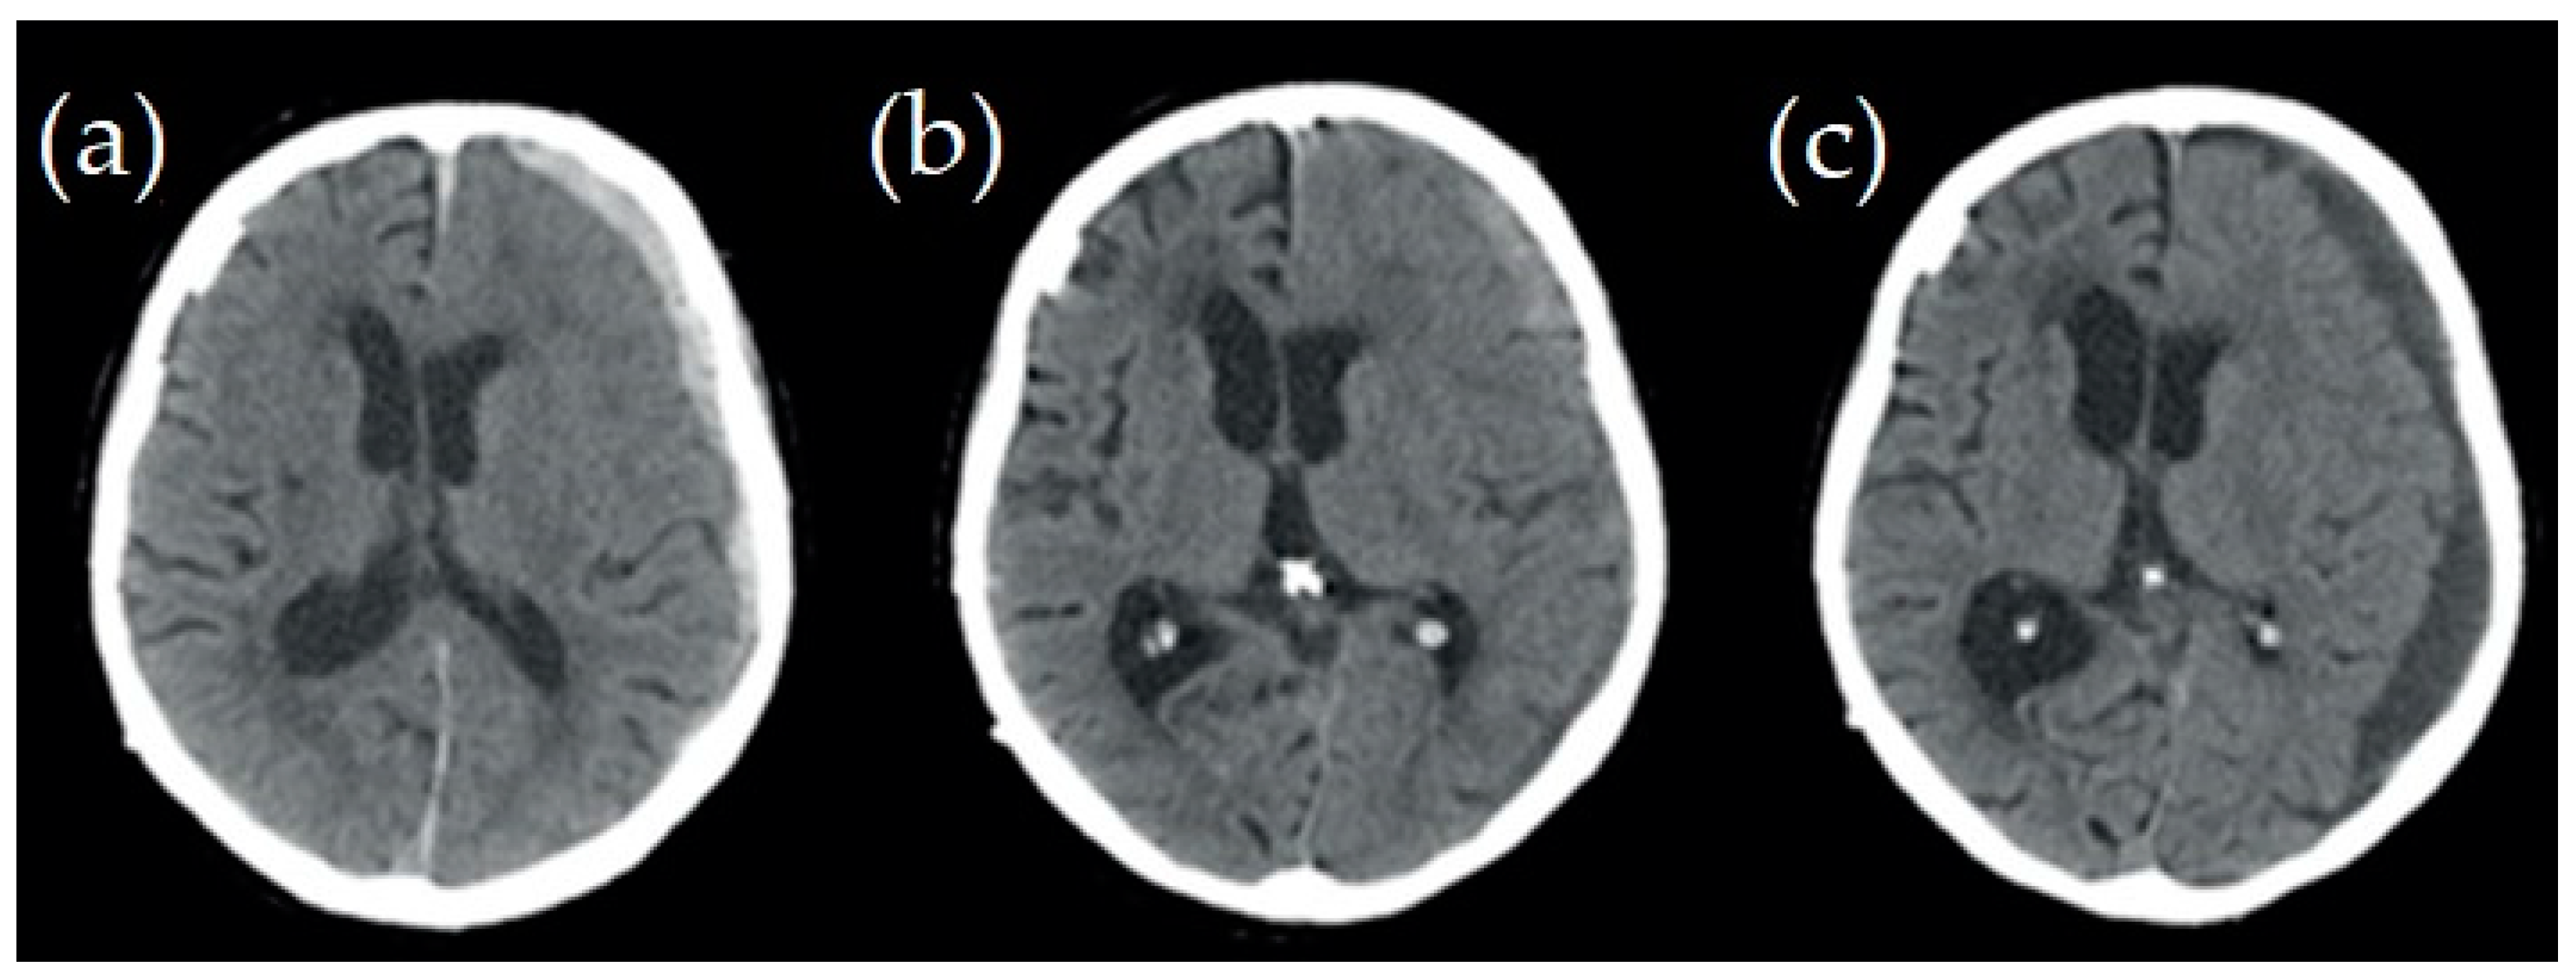

2.1. Case Studies